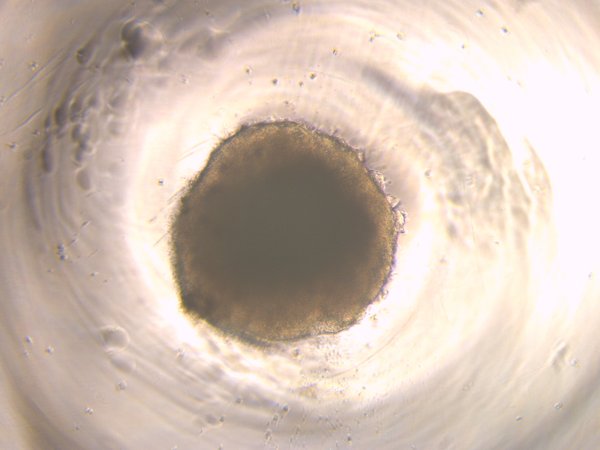

Disease Model A1A

A1A

TUBA1A mutation, Day 10